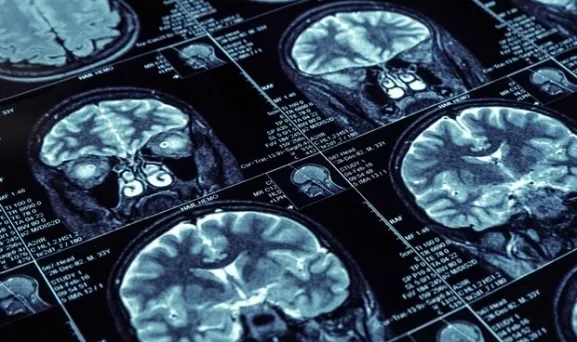

Descubren un nuevo gen relacionado con el riesgo de desarrollar Alzheimer

Las variaciones de un segmento de un gen llamado Mucina 6 están asociadas a la enfermedad de aparición tardía

Investigadores de la Universidad de Kentucky (Estados Unidos) han descubierto un gen que puede ayudar a explicar una gran parte del riesgo genético para desarrollar la enfermedad de Alzheimer, según un estudio publicado en el Journal of Neuropathology & Experimental Neurology.

El alzhéimer de inicio tardío, la forma más común de la enfermedad, es una afección neurológica devastadora con aspectos de riesgo hereditario que no se comprenden por completo. Desafortunadamente, la complejidad del genoma humano y las deficiencias de investigaciones anteriores son factores limitantes, por lo que algunos fenómenos genéticos no se estudiaron por completo en estudios anteriores.